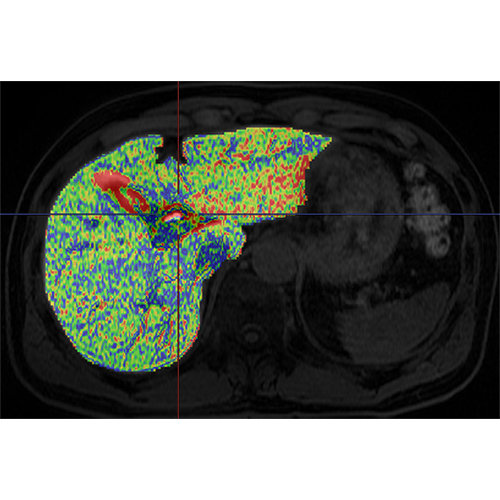

了解更多